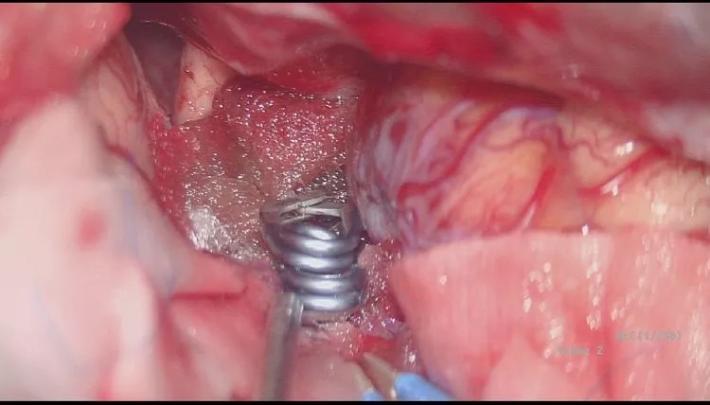

并行自752夹子上方向近端置742动脉瘤夹一枚,并列自硬膜补片外侧夹闭BBA,手术顺利! 那么脉前A怎么保全呢?

脉前A的保留是术中的一个难题,我们采取硬膜瓣半侧开叉(黄箭头),让脉前A(粉红箭头)由开叉处穿出,避免包裹夹闭后扭曲压迫而致闭塞,术中拟在阻断IcA颅外段与同侧A1的低灌注压状态,采用“L”型异形夹多可顺利夹闭BBA,保留后方脉前A通畅!

撤除A1与同侧颈内A临时阻断夹,探查见脉前A保留完整,术区止血!

探查桥血管通畅,STA(黄箭头)→M2(绿箭头)充盈良好! 结束颅内操作,下面再造影看下BBA有否残留或局部颈动脉管腔有否狭窄,桥血管通畅就可以结束了。